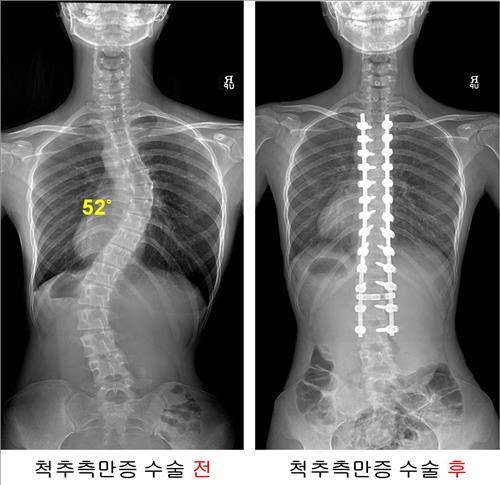

"ôÃßÃø¸¸Áõ ¼ö¼úȯÀÚ 85%°¡ 10´ë ¿©Çлý"

¼¿ï¾Æ»êº´¿ø ôÃßÃø¸¸Áõ ȯÀÚ 1õ¸í ºÐ¼®°á°ú (¼¿ï) ±è±æ¿ø ±âÀÚ = Ç㸮°¡ SÀÚ ÇüÅ·Π±¸ºÎ·¯Áø 'ôÃßÃø¸¸Áõ'À¸·Î ¼ö¼ú¹Þ´Â ȯÀÚÀÇ 85%´Â 10´ë ¿©ÇлýÀ¸·Î ³ªÅ¸³µ´Ù. ¼¿ï¾Æ»êº´¿ø ôÃßÃø¸¸Áõ¼¾ÅÍ ÀÌÃἺ ±³...